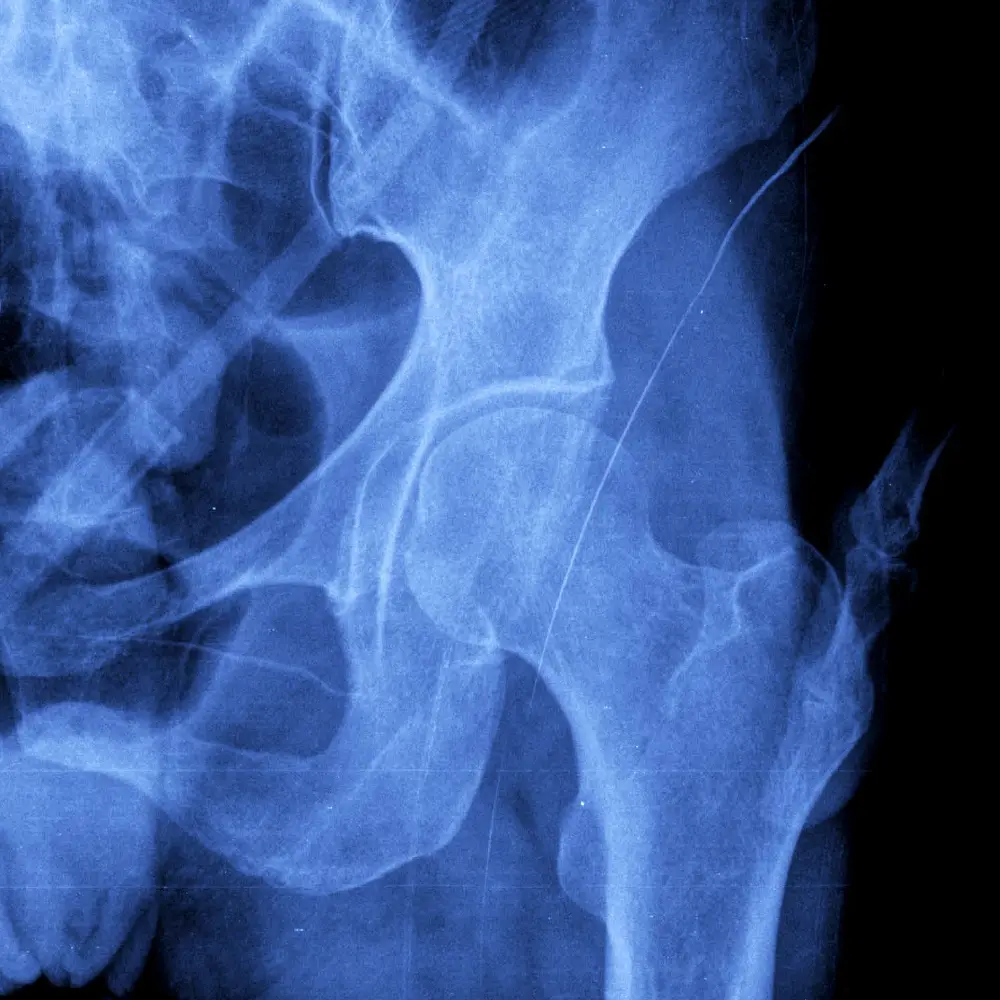

Determining the Best Cementation Techniques for Hip Replacements

The use of cemented versus cementless joint prostheses in total hip replacement has undergone exhaustive investigations over the past several decades, with researchers seeking to establish guidelines for one approach having greater patient outcomes over the other. Columbia physicians, including Drs. H. John Cooper, Roshan P. Shah, and Mouhanad El-Othmani, published a comprehensive research report on the topic wherein they characterized evidence-based modern practice in femoral stem cementation in primary hip arthroplasty. The review showed that while the cementing process adds technical complexity to total hip arthroplasty, growing evidence supports its use in certain cohorts, and surgeons should have a thorough understanding of modern cementation techniques.

Image of a cemented femoral stem in total hip arthroplasty